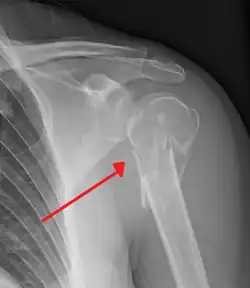

Proximal

Proximal humerus fractures most often occur among elderly people with osteoporosis who fall on an outstretched arm.[9] Less frequently, proximal fractures occur from motor vehicle accidents, gunshots, and violent muscle contractions from an electric shock or seizure.[10][5] Other risk factors for proximal fractures include having a low bone mineral density, having impaired vision and balance, and tobacco smoking.[11] A stress fracture of the proximal and shaft regions can occur after an excessive amount of throwing, such as pitching in baseball.[6]

Definitive diagnosis of humerus fractures is typically made through radiographic imaging. For proximal fractures, X-rays can be taken from a scapular anteroposterior (AP) view, which takes an image of the front of the shoulder region from an angle, a scapular Y view, which takes an image of the back of the shoulder region from an angle, and an axillar lateral view, which has the patient lie on his or her back, lift the bottom half of the arm up to the side, and have an image taken of the axilla region underneath the shoulder.[9] Fractures of the humerus shaft are usually correctly identified with radiographic images taken from the AP and lateral viewpoints.[12] Damage to the radial nerve from a shaft fracture can be identified by an inability to bend the hand backwards or by decreased sensation in the back of the hand.[5] Images of the distal region are often of poor quality due to the patient being unable to extend the elbow because of pain. If a severe distal fracture is suspected, then a computed tomography (CT) scan can provide greater detail of the fracture. Nondisplaced distal fractures may not be directly visible; they may only be visible due to fat being displaced because of internal bleeding in the elbow.[7]

Humerus fractures are among the most common of fractures. Proximal fractures make up 5% of all fractures and 25% of humerus fractures,[9] middle fractures about 60% of humerus fractures (12% of all fractures),[12] and distal fractures the remainder. Among proximal fractures, 80% are one-part, 10% are two-part, and the remaining 10% are three- and four-part.[22] The most common location of proximal fractures is at the surgical neck of the humerus.[3] Incidence of proximal fractures increases with age, with about 75% of cases occurring among people over the age of 60.[11] In this age group, about three times as many women as men experience a proximal fracture.[23] Middle fractures are also common among the elderly, but they frequently occur among physically active young adult men who experience physical trauma to the humerus.[12] Distal fractures are rare among adults, occurring primarily in children who experience physical trauma to the elbow region.[7]